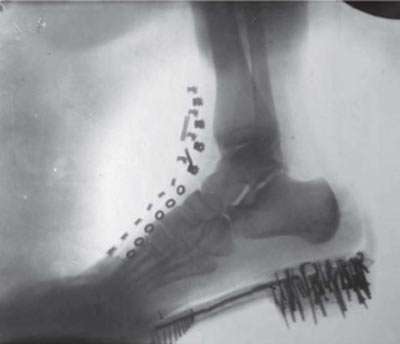

Imprint of a human foot was made by Tesla in 1896 with X-rays produced by his own vacuum tube Nikola Tesla experimented with high frequency high voltage currents and found them to be harmless and beneficial to the human body. At that time high frequency currents were deemed lethal, but Nikola Tesla proved otherwise, having applied these currents to himself. He gave demonstrations, placing himself in the electrical circuit which lighted lamps and heated wires to incandescence. He said: “I have produced electrical oscillators which were of such intensity that when circulating through my arms and chest they have melted wires which joined my hands, and still I felt no inconvenience. I have energized with such oscillations a loop of heavy copper wire so powerfully that masses of metal, and even objects of an electrical resistance specifically greater than that of human tissue, brought close to or placed within the loop, were heated to a high temperature and melted, often with the violence of an explosion, and yet into this very place in which this terribly destructive turmoil was going on I have repeatedly thrust my head without feeling anything or experienced any inconvenience.” Amazing indeed, but which electrical engineer nowadays have ever heard of this? Does this not warrant further investigation? Noting that his high frequency currents were wiping out microbes, he tells us: “My high frequency currents have bactericidal effects. So it has become a daily routine for the inventor to take off his clothes, stand in front of his coils and a prickly corona would envelop his body and restore his health.” Nikola Tesla gave lectures and published articles about these Alternate Currents of High Potential and High Frequency, both electrical engineers and medical professionals, because Tesla saw the potential for therapeutic treatments using these currents. This was the start of many years of electrotherapy using these Tesla currents by doctors and dentists, with great success. Because these apparatus were usually large and bulky, Tesla also developed a small oscillator, about a foot (30 cm) long for use inside a home. This also became popular, but he didn't commercialize it.